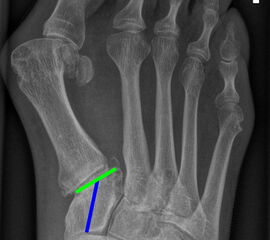

Gelenkflächenwinkel

DMAA (Distal metatarsal artikular angle, Syn. Gelenkflächenwinkel): Winkel zwischen der Achse des Os metatarsale I (rot) und dem Lot auf die distale Gelenkflächenebene (blau) des Os metatarsale I. Die Gelenkflächenebene (grün) wird definiert durch zwei Punkte, welche die mediale und laterale Begrenzung der Gelenkfläche definieren (Norm: <10° 5). Die Projektion des DMAA ist stark abhängig von der Rotation des Os metatarsale I 7. Daher ist bei der operativen Behandlung des Hallux valgus eine Beurteilung häufig erst nach Korrektur der Pronationsstellung des Os metatarsale I möglich. Tendenziell wird der DMAA auf präoperativen Röntgenaufnahmen überschätzt.